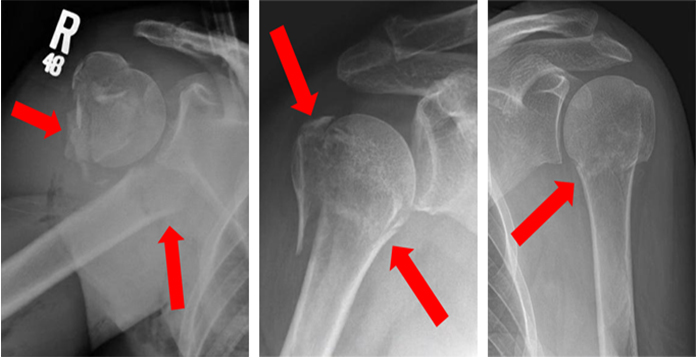

Investigations

- X-rays

Clavicle Fractures

Most clavicle fractures can be treated non-surgically. However, a compound or severly comminuted fractur will require surgery. Surgery typically involves fixing the fracture with plates, screws or rods inside the bone.

Proximal Humerus Fractures

Fractures of the proximal humerus can be treated without surgery in case the bone fragments are not displaced. Surgery is usually required, if the fragments are shifted out of position. Surgery may involve fixing the fracture fragments with plates, screws, or pins; In some cases where there are multiple fracture fragments shoulder replacementis done.

Scapula Fractures

Most of the scapula fractures can be treated without surgery. Treatment involves immobilization with a sling or shoulder immobilizer, icing, and pain medications. About 20% of scapula fractures may need surgery when they are associated with proximal humerus or clavicle Fractures. These fractures are fixed with plates and screws.